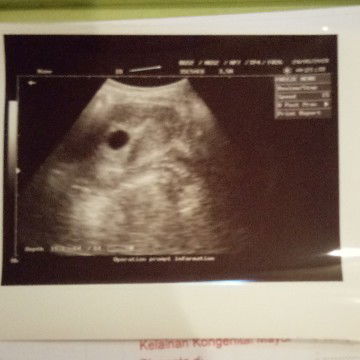

menghitung usia kandungan dan usg

Bund aku skrg lagi bingung nih di bidan perkiraan kandungan aku 7week karena di hitung dari hpht, terus aku usg di dokter kandungan usia kehamilan aku 5week kalo dilihat dari hasil usg nya soalnya belum terlihat ada janin nya, jadi yg bener usia kandungan aku yg mana ya bun? Terus pas usg kata dokter kandungan nya kantung nya itu aga turun tidak sesuai posisi, apa itu ga apa2 ya bun sama keadaan janin aku dlm kandungan?

usg

Bund kalo usia kandungan 7 week apa sudah terlihat kalo usg?